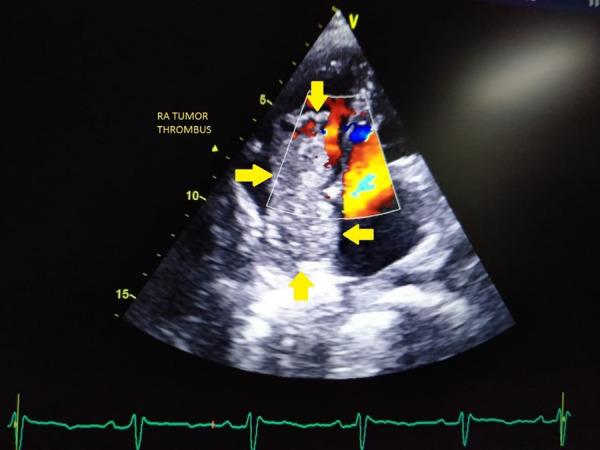

Hepatocellular Carcinoma with Inferior Vena Cava and Right Atrium Tumor Thrombus.

Hepatocellular carcinoma (HCC) is one of the leading causes of cancer and cancer related deaths worldwide. Metastasis of HCC into the cardiac cavity is mostly caused by direct tumor thrombus invasion through the major hepatic veins and of vena cava inferior with continuous extension into the right cardiac cavity. Right heart metastasis without invasion of inferior vena cava (IVC), which may be caused by haematogenous spread of cancer cells, is rarely reported. We report a case of HCC with IVC and right atrium (RA) thrombus in a patient who presented to us with decompensated cardiac failure. Strikingly, the patient was young and with negative serum HBsAg, and anti-HCV results. Our case highlights a rare presentation of metastatic intracardiac tumor thrombus involving the RA in advanced HCC without any symptoms of cardiac failure, and henceforth, the role of screening echocardiography for all patients with advanced HCC especially with vena caval involvement to rule out intracardiac thrombus.